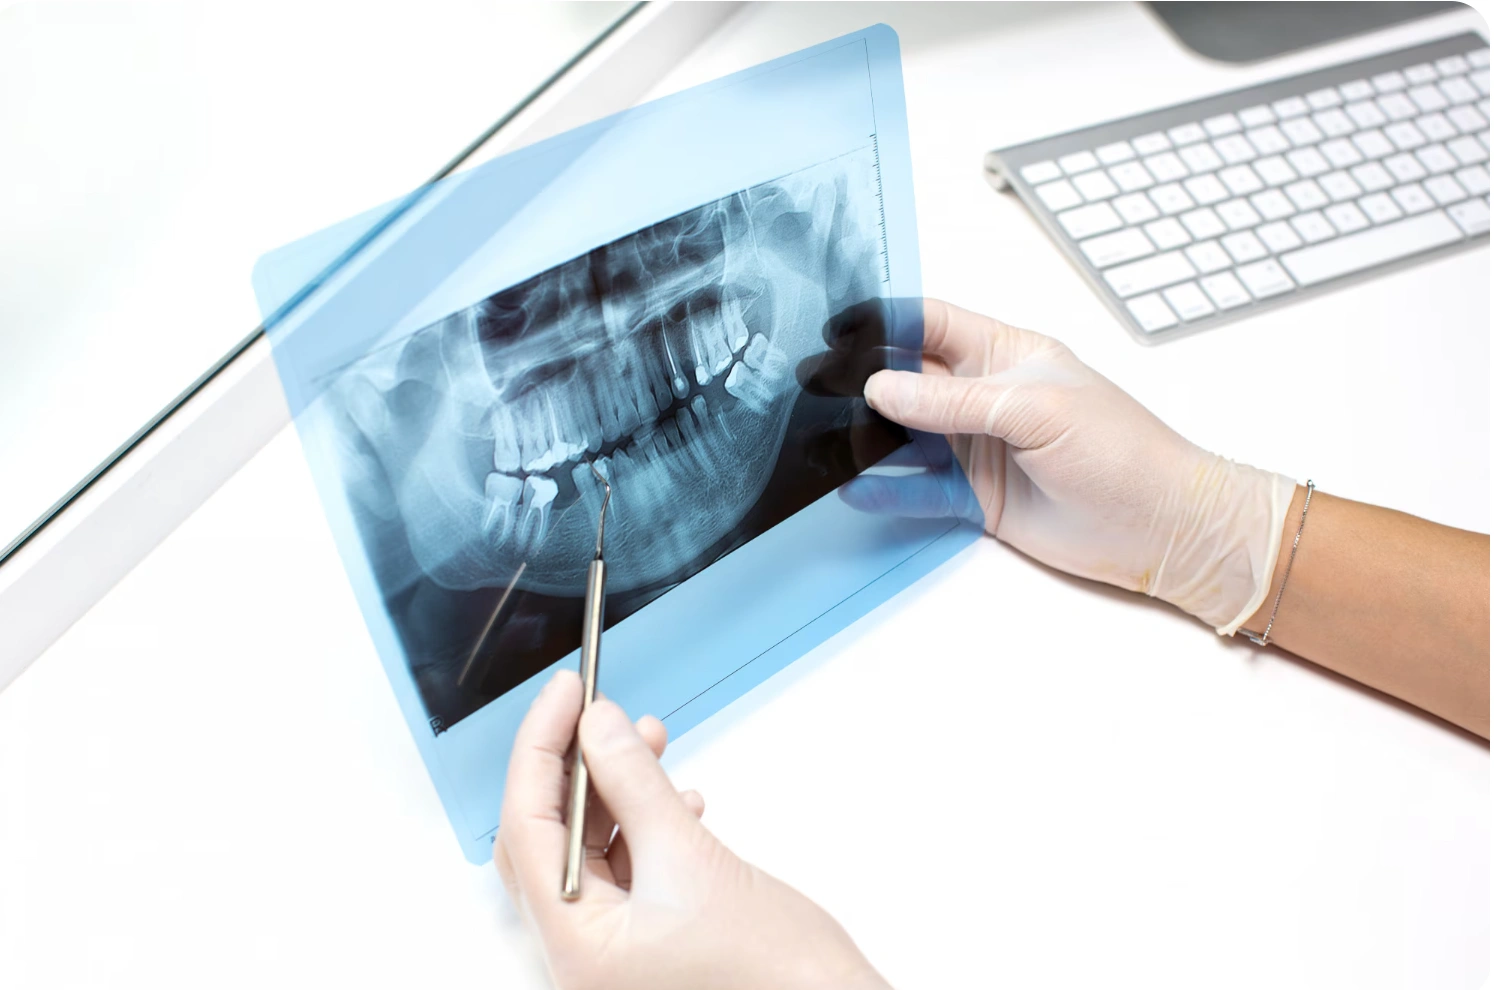

In many places, implants are still placed using only 2D X‑rays and the dentist’s feel for the bone. It can work, but there’s always some uncertainty about exactly how much bone is available, where the nerve runs or how close the sinus is.

At Gelos Dentistry, we start with an in‑house 3D CBCT scan. This gives us a clear, three‑dimensional view of your jaws – bone height, width, density, nerve canals, sinus spaces – everything we need to see before touching the bone. On a computer, we then plan where each implant should go, at what angle, and to what depth.

If implants look like a good option, we move to a 3D CBCT scan. The scan is quick and painless; you simply stand still while the machine rotates around your head. Within minutes, we can see detailed cross‑sections of your jaws on the screen.